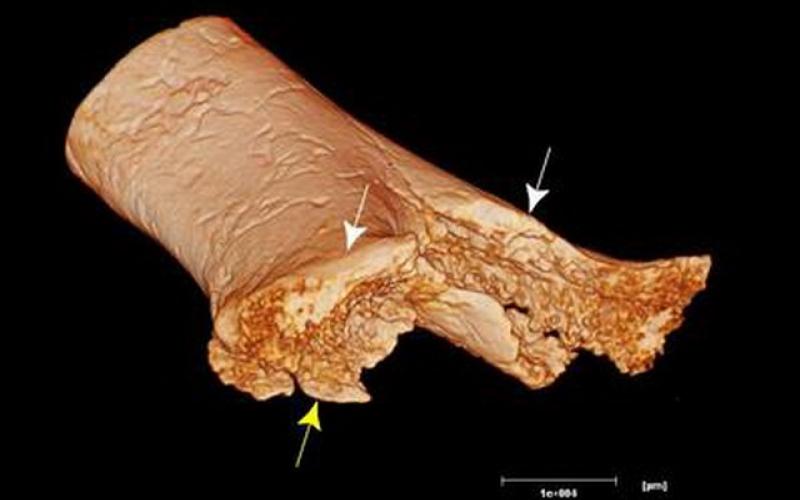

حدود ۳۱ هزار سال پیش در جنگل های مه آلود جزیره برونئو، ابزار جراحی ساخته شده از سنگ، یک استخوان را لمس کردند و با قطع یکی از اعضای بدن یک فرد جوان، جان او را نجات دادند.

به گزارش سیتنا، محققان شواهدی برای اولین جراحی قطع عضو شناخته شده، بدون وجود ابزارهای مدرن جراحی، آنتیبیوتیکها و مسکنهای امروزی در دهها هزار سال قبل یافتهاند.

احتمالا جراح باستانی، برای بریدن پا از یک ابزار سنگی یا استخوانی استفاده کرده است. اگرچه این تیم هنوز ابزاری که شبیه اره باشد و از استخوان ساخته شده باشد، در عصر حجر را پیدا نکرده است.